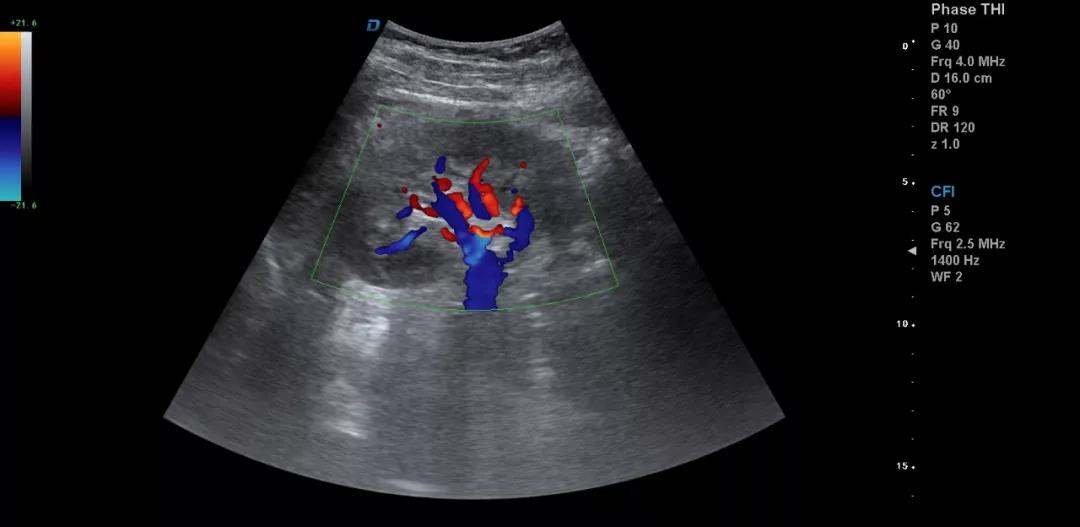

典型圖片、經(jīng)典病例圖片、動態(tài)影像資料積累的多了分析總結之后就提高了。疑難病例資料積累后,可以隨訪病人,然后總結得到的臨床資料和病理結果。

有了手術結果和病理才會有真正的提高。按器官、按系統(tǒng)、按學科進行總結每一個、每一類疾病正常及異常圖片就是知識的積累。